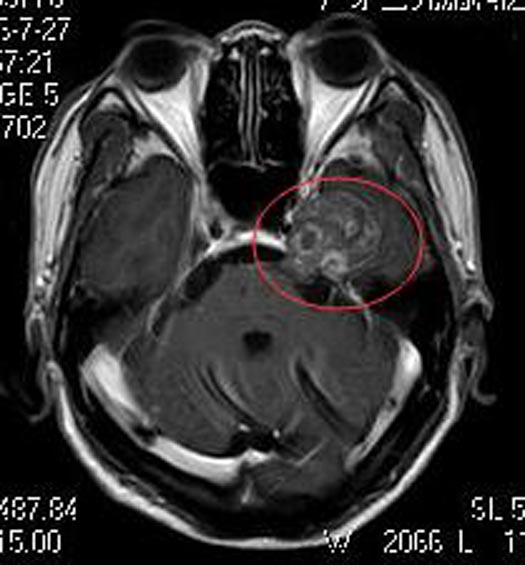

脑肿瘤可不是小事,儿女们认为不能再拖了。广东三九脑科医院头颅MR检查提示:左侧鞍旁三叉神经走行区占位性病变,病变边界清,与左侧三叉神经走行关系密切,大小约2.8cm×3.4cm,增强后病灶呈不均匀强化,其中示多个小环状强化灶,邻近左侧颞叶受压,考虑神经鞘瘤可能性大。